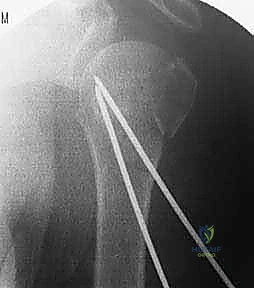

4. إدخال الأسلاك المعدنية (K-wires)

بمجرد أن يصبح الكسر في الوضع المثالي، يتم إدخال أسلاك كيرشنر (Kirschner wires) الدقيقة عبر الجلد مباشرة إلى العظم. يتم توجيه هذه الأسلاك بزوايا هندسية مدروسة لضمان أقصى درجات الثبات. عادة ما يتم استخدام 2 إلى 4 أسلاك.

5. التحقق من الثبات وقص الأسلاك

بعد وضع الأسلاك، يتم تحريك الكتف بحذر للتأكد من ثبات الكسر التام. بعد ذلك، تُقص نهايات الأسلاك وتُترك بارزة قليلاً فوق الجلد (أو تُدفن تحت الجلد مباشرة) لتسهيل إزالتها لاحقاً.

6. التقييم النهائي والإغلاق

تُؤخذ صور شعاعية نهائية لتوثيق نجاح العملية، وتُغطى مواقع دخول الأسلاك بضمادات معقمة.

صور إضافية من داخل غرفة العمليات توضح دقة الإجراء: